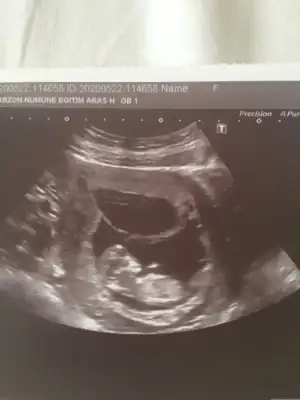

Evet paralele yakın açıda kız oldugunu düşünüyorumHayırlı bayramlar![]()

Ikra meyra başka bir açıdan daha resim atıcam o bacak arası kısmında görülen net beyaz çizgi nub mu oluyor

Çok teşekkür ederimEvet paralele yakın açıda kız oldugunu düşünüyorum